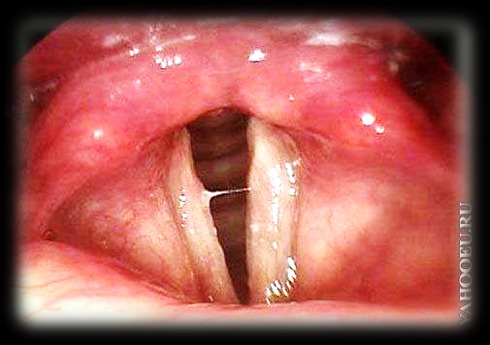

Ларингит